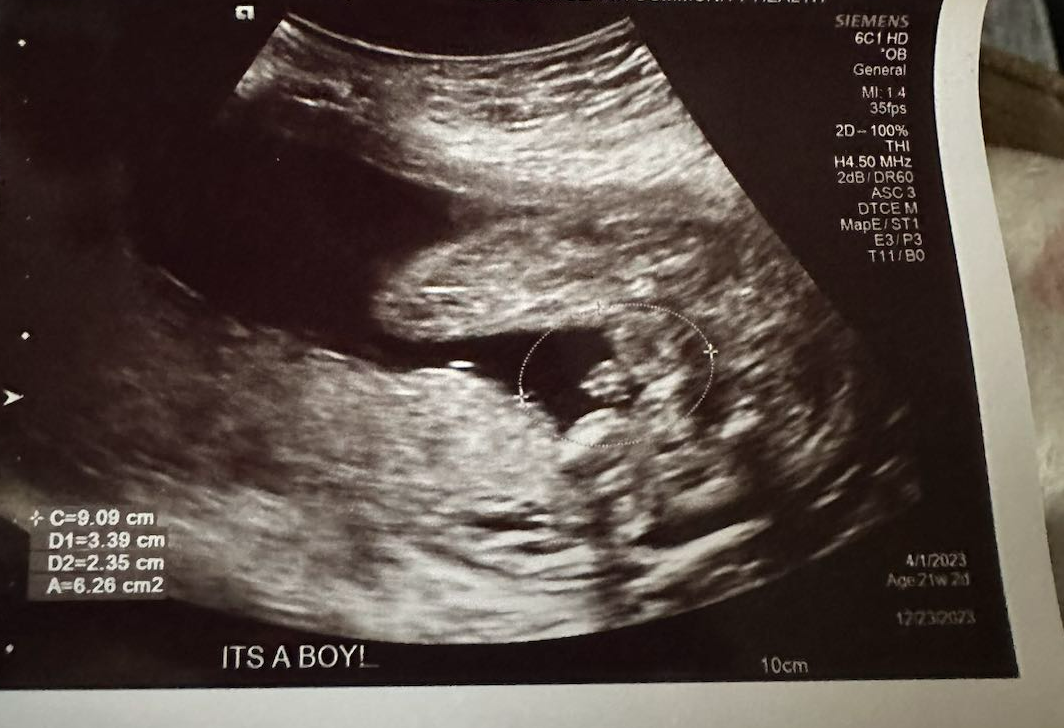

来自密苏里州的爱妈M今天如期前往妇产科进行了检查,宝宝已经21周大了。在检查中,可以清晰地看到了一个可爱的小男孩!在美国PGS技术不仅可以检测胚胎的染色体异常,还可以实现性别的选择。

这项技术可以帮助准父母能够更好地规划自己的家庭。和爱妈M匹配的准妈妈非常的高兴,她目标是能够迎来属于自己的两个宝宝,期待着她未来家庭的美好发展!